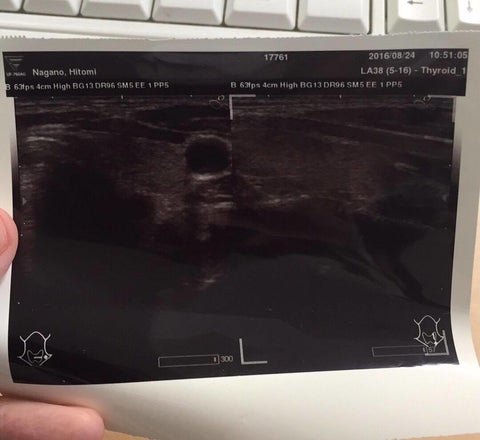

今日、私は糖質制限仲間の医師を訪ねて、病院を受診してきました。 もうずっと。1年は検査していない、自分のがんがどうなったのかを診てもらうためです。 20代の時から、甲状腺が大きいと指摘されていて経過観察中でした。 子供を3人産んで、声のカスレの頻度が増したことを自覚し、若干不安を覚え、受診したのが平成26年。 その時「甲状腺乳頭がん」というありがたくない診断名をいただいた私。 やっぱりかと不安な予想が的中。 でも甲状腺乳頭がんは経過が穏やかな「ラッキーながん」であること。サイズ的にも、そんなに大きくないので、「経過観察」が一番よい選択肢であることを聞き、非常に複雑な気持ちに。 「何にもしないでただ様子を見るっていうこと?」 不安でしたね~。 薬を飲むとか、切るとか、放射線を当てるって、「治療をしている感」がしっかりあって、不安ながらも安心できるのですが、 「なんもすること、ない」 って皆さんもその立場になってみると思うとわかると思いますけど、すごく不安ですよ~!! すでに糖質制限中だったので、私は「これはシャレにならない。頑張らなきゃ」と今まで以上に糖質制限に対して真剣に考えるようになったのは、言うまでもありません。 言えませんでした。家族には。友人たちにも。 糖質制限を真剣にやりだしてからの発覚。 糖質制限が、間違いなく正しいとすでに確信していた私ですが、 病気をカミングアウトして、糖質制限をやめろ!糖質制限のせいだ!と言われることでエネルギーを使いたくなかった、というのがあります。 それに乳頭がんで、今すぐ手術とか、そういうわけでもなさそうなので。もしかしたら、糖質制限でがんと勝てるかも、無駄に家族に心配かけることはしなくてもいいのでは、と思いました。 がんと公表することで、糖質制限をするとがんになる、というイメージをみんなに更に強くしてしまったり、またいらぬ誤解を受けるかもしれないと、もしかしたら家族も批判を受けるかもしれない、と思うと。 怖くて言えませんでした。 こんなに、糖質制限について発信していて、コータも前面に出しているのに「なんて卑怯な奴」と言われても仕方ないです。自分は隠しているなんて。 ここ半年で、私、結構変わったなと思うのですが。 勉強をして、いろいろ実践して。食事について真剣に考えてみました。 本当に糖質制限でがんと勝てるのか。 ひっそりと自分で観察してみたかったのもあります。 今日の診察は、ちょっと怖かったですね。 自分で一生懸命頑張って、「正しく食事している」という気持ちはあっても、 「これでがんが大きくなっていたらマジで笑えない」 「矛盾しているし、恥ずかしい」 そんな気持ちから、経過観察のエコーも足が遠のき、放置すること1年。 (偉そうなことを言っていても、自分のことになると、こんなものです) 知り合いの医師に診てもらうということで、もう隠しようも逃げようもないし、 結果は受け止めよう、と覚悟しての受診でした。 結果です。 「がん、ないよ」 甲状腺の左様、真ん中に確かにあった、がんは、すっかり消えてなくなっていました!! 「うそ~!!消えたってことですか?」 びっくりしました。こんなことって本当にあるんですね。 大きくなっていなきゃいいやって思っていましたが、まさか消えているなんて。 嬉しいというより、本当にびっくりしました。 皆さんに、こんないい報告ができること、心から嬉しく思います。 「ありがとう」 感謝の気持ちでいっぱいです。子の奇跡を、コータにも。あとに続く方々のためにも。しっかりと抱きしめて皆さんのお役に立つことで、いただいた奇跡に感謝して恩返ししていきたいです。 命、繋がれ。 こんな私に、糖質制限を伝えるお仕事。 これからもさせていただいて、皆さん、良いでしょうか。 頑張れ!と言ってくださる方。ありがとうございます!がんばります! クラウドファンディング、達成まであと少し。皆さん良かったら、応援してください! 神様、ありがとう!! の